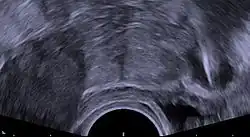

Inmediatamente antes de la inserción, el clínico realizará un examen pélvico para determinar la posición del útero.[23] Tras el examen pélvico, se mantiene abierta la vagina con un espéculo.[39] Se utiliza un tenáculo para estabilizar el cuello uterino y el útero.[39] Se puede utilizar un sonda uterina para medir la longitud y la dirección del canal cervical y el útero con el fin de disminuir el riesgo de perforación uterina. El diu se coloca utilizando un tubo estrecho, que se introduce a través del cuello uterino hasta el útero. Unos hilos cortos de monofilamento de plástico/nylon cuelgan del útero hacia la vagina. El clínico recortará los hilos para que sólo sobresalgan 3 o 4 cm del cuello uterino y permanezcan en la parte superior de la vagina. Los hilos permiten a la paciente o al clínico comprobar periódicamente que el diu sigue en su sitio y facilitan la extracción del dispositivo.[23]